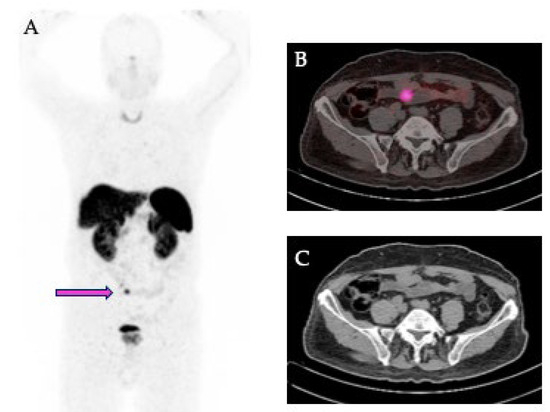

The PET/CT data in DICOM format were analyzed by LIFEx software (developed at CEA, Orsay, France, http://www.lifexsoft.org, last accessed on 20 May 2025) [26], obtaining a volume of interest (VOI) of each primary lesion. For this purpose, a three-dimensional region was drawn around each lesion by using an automatic segmentation method that groups all spatially connected voxels within a predetermined threshold. A threshold of SUV > 2.5 was used, based on the mean SUVmax of the mediastinal blood pool plus 2 SD (Figure 1).

Figure 1. Representative images of a 68Ga-DOTATOC PET/CT scan in a patient with NET of the ileum. (A) Maximal intensity projection view showing the primary tumor in the ileum (pink arrow). (B) Transaxial fusion image showing the segmentation (pink) of the primary tumor. (C) Corresponding transaxial CT image.